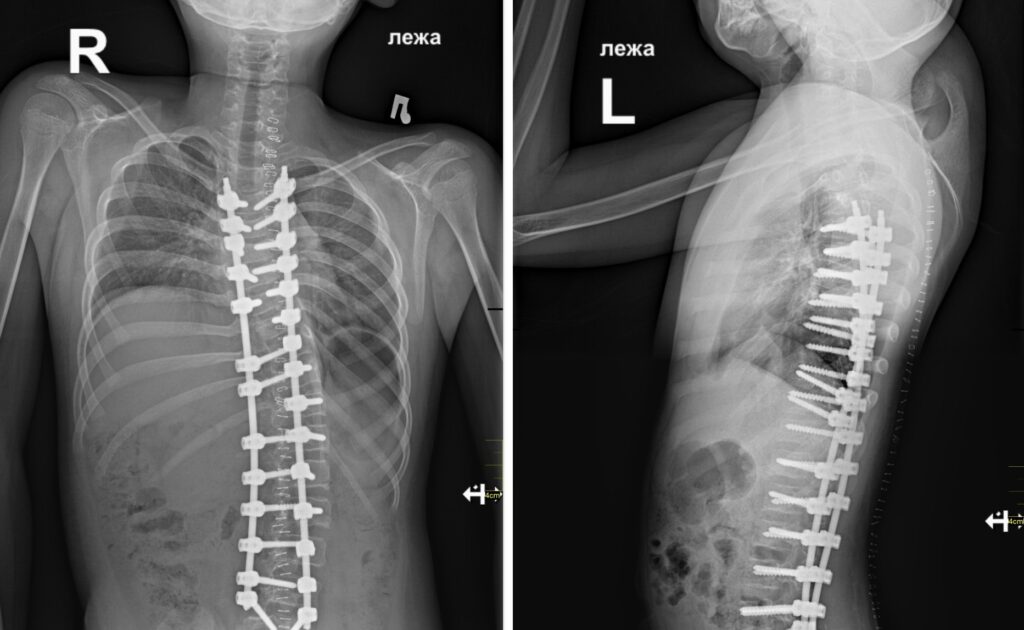

В Новосибирском НИИТО им. Цивьяна прооперировали 12-летнего мальчика из Тывы с тяжелой травмой позвоночника, полученной в результате ДТП. Об этом сообщает официальный сайт учреждения 16 апреля.

В страшную аварию семья ребенка попала 10 лет назад – в 2015 году. С тех пор мальчик передвигается в инвалидной коляске, деформация его позвоночника достигла критических 143 градусов. При таком искривлении человек не может не то что ходить, но даже сидеть.

Хирурги вмонтировали в позвоночник металлоконструкцию, благодаря которой удалось скорректировать искривление до 32 градусов. При исходных 143 градусах это хороший результат.